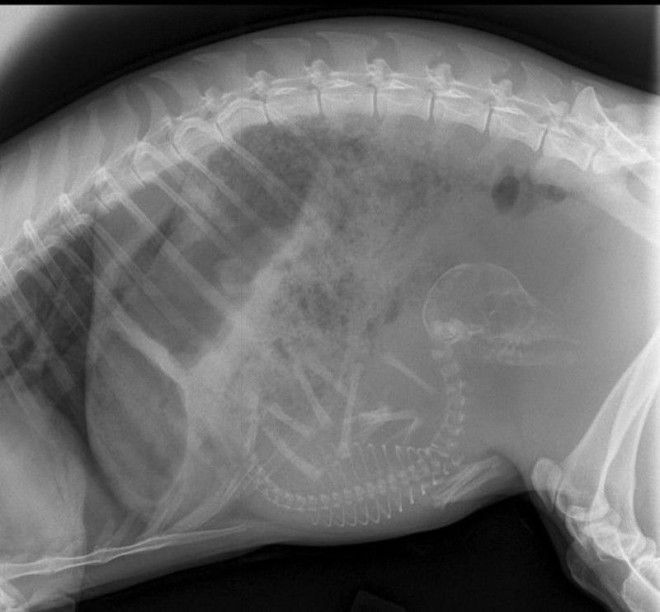

3. Беременная кошка